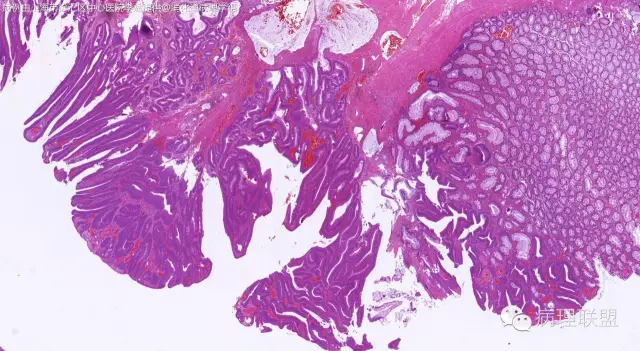

管状~绒毛状腺瘤伴低级别上皮内瘤变,黏膜下层部分腺体破裂黏液外溢伴黏液糊形成。

本例部分腺体异位到黏膜下层。

@周泉分析的在理,但绒毛管状腺瘤有这么粗大的平滑肌觉的也不是很多见。

@陈真伟 这可能是腺体异位,间质出血等多种原因导致的黏膜肌增生吧。这个俺就说不来了

@李斌 李大夫的片子一向漂亮,有赏心悦目的感觉,必须赞一个。这例同意周大夫的意见,低级别绒毛管状腺瘤伴腺体破裂导致的黏液外溢。粘液池周围可见血管扩张淤血、含铁血黄素沉积、肉芽组织形成,提示发生过蒂扭转和出血,这常是造成假浸润、粘液溢出的原因。比较大的绒毛管状腺瘤会有分叶结构,会有比较粗大的平滑肌干,但缺少P-J息肉叶脉样从主干再分支出来的细平滑肌束。作为错构瘤性息肉的一种,P-J息肉的腺体可以分支、扩张、腺腔不规则,但没有细胞异型性,伴发异型增生时,局部出现细胞异型性但不会像这例这样齐刷刷都是异型的腺体。